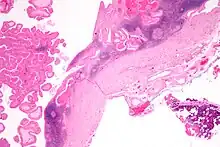

The appearance of this tumor under the microscope is unique. There are cystic spaces surrounded by two uniform rows of epithelial cells with centrally placed pyknotic nuclei. The cystic spaces have epithelium referred to as papillary infoldings that protrude into them. Additionally, the epithelium has lymphoid stroma with germinal center formation.

Low magnification micrograph of a Warthin tumor arising from the parotid gland.

Low magnification micrograph of a Warthin tumor arising from the parotid gland. -